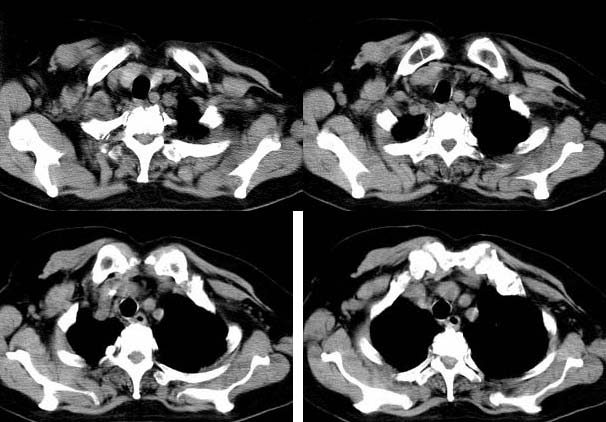

标题: CT8224女,76,咳,发热,糖尿病患者。

请大家讨论右下肺占位性质。ct值约35-55hu

右肺门后侧软组织肿块,内见点状钙化,年龄76,ct值约35-55hu ,考虑肺癌可能

右肺门后侧环绕支气管的软组织肿块,内见点状钙化,远端有阻塞性炎症,年龄76,ct值约35-55hu ,考虑右肺中心型肺癌。建议支气管镜鉴。

右下肺,右肺门后方见团块状软组织密度影,边缘呈分叶状,其内见斑点状钙化,肿块内部支气管腔闭塞。肿块后方可见胸膜尾征,外侧方见斑片状模糊阴影。右肺门淋巴结增大。

考虑:右侧中央型肺癌伴阻塞性肺炎及右肺门淋巴结转移